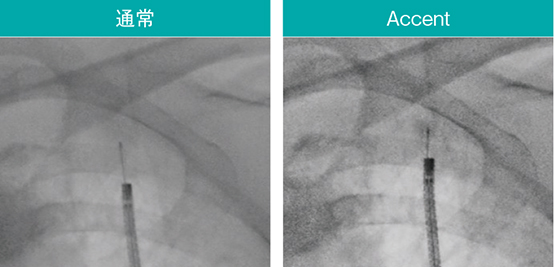

内視鏡検査に用いるデバイスは通過性や柔軟性が優先され、透視下での視認性に課題がある製品もある。Ultimax-i の新画像処理条件「Accent」は、ガイドシースや生検針などのデバイスや関心領域を強調し、より手技がしやすい環境を提供する。実際の透視像(図7〜9)でも、Accent適用により腫瘤やEBUSプローブ、ガイドシース、ブラシなどのデバイスが明瞭に確認できる。

図9 Accentによるブラシや関心領域の強調

スコープ:BF-MP290、細胞診ブラシ:BC-205D-2010(オリンパス社製)